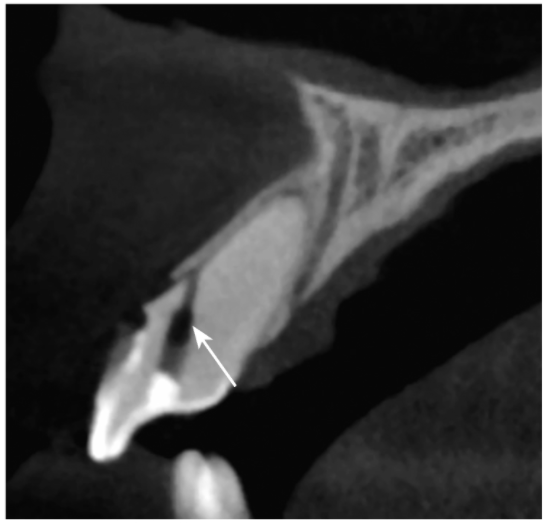

图2-2-6 B1弥漫性钙化伴侧穿

CBCT矢状位示B1弥散性钙化bccbch币,自舌侧窝至唇侧牙颈部见侧穿(白色箭头)